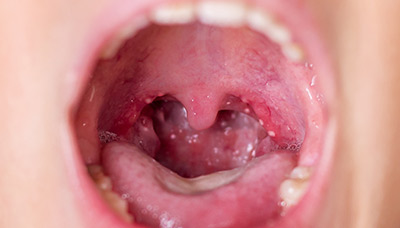

Фолликулярная ангина – воспалительное заболевание, поражающее лимфоузлы и миндалины, вызывающее неприятные симптомы и ухудшающее здоровье.